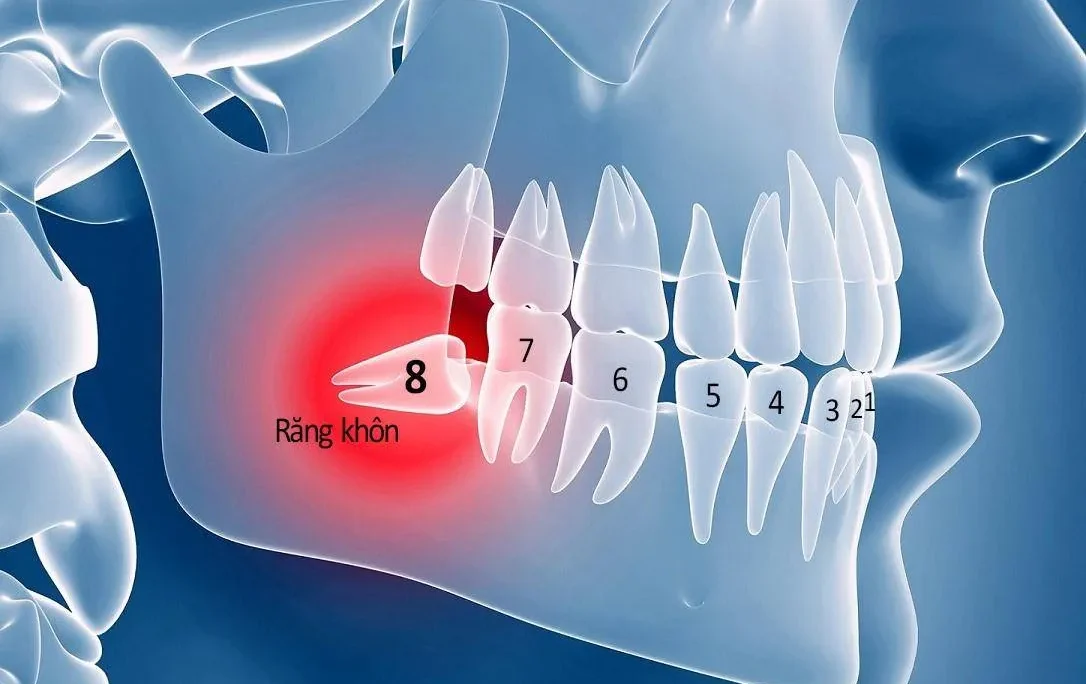

Kỹ thuật cấy ghép Implant được chỉ định trong các trường hợp sau:

- Bệnh nhân mất răng có nhu cầu làm răng cố định mà không cần mài răng thật;

- Người bị mất răng không muốn dùng hàm tháo lắp. Các răng còn lại trên hàm không đủ sức để làm trụ cầu. Đặc biệt là trong trường hợp bị mất nhiều răng;

- Người bệnh có nhu cầu làm răng giả. Tuy nhiên muốn bảo tồn, không gây tiêu xương hàm ở những vùng răng đã mất đi.

Chống chỉ định tuyệt đối với phương pháp Implant là:

- Phụ nữ mang thai;

- Người bệnh tiểu đường không được kiểm soát;

- Trẻ em dưới 17 tuổi;

- Người bệnh đang có viêm nhiễm tiến triển ở vùng đặt Implant.